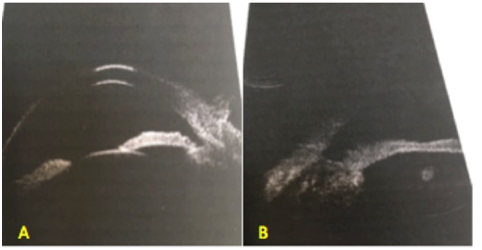

Ultrasound Biomicroscopy (UBM) showed Figure 2 mass in infero-temporal quadrant with ciliary body infiltration from external lesion with no involvement of iris tissue. Angles were open with external ocular coats being thickened. AS-OCT Figure 3 showed irregular iris surface along with involvement of ciliary body.

Figure 2 UBM showed a mass in infero-temporal quadrant with ciliary body infiltration from external lesion with no involvement of iris tissue.